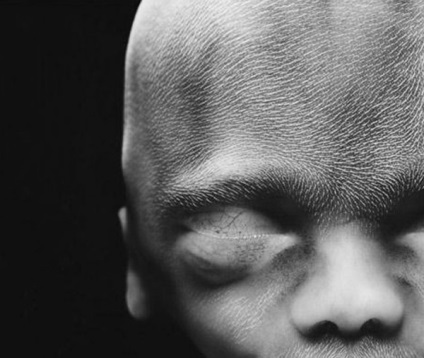

18 săptămâni. Germenul poate percepe sunetele din lumea exterioară

20 săptămâni. Înălțimea de aproximativ 20 cm. La capul de păr începe să apară

36 săptămâni. O lună mai târziu, copilul se va naște.